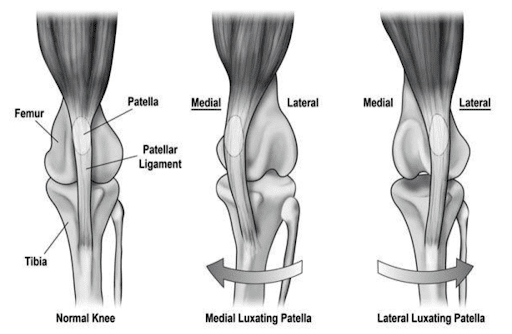

Figure 2: Medial vs Lateral patella luxation (Holt 2017, https://scholar.utc.edu/cgi/viewcontent.cgi?article=1108&context=honors-theses)

When the patella is “luxated”, the kneecap is essentially displaced. Instead of just sliding up-and-down, it can move from side-to-side. Most kneecaps displace towards the animal’s body (i.e. medially/ inwards), this is more common in smaller breeds. In some cases, the kneecap displaces away from the body (i.e. laterally/ outwards), this is more common in larger breeds. About 50% of the dogs with patella luxation are affected in both legs.